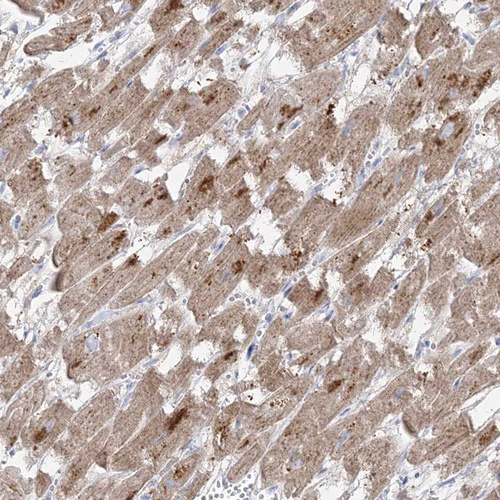

Immunohistochemical staining of human heart muscle shows moderate cytoplasmic positivity in cardiomyocytes.